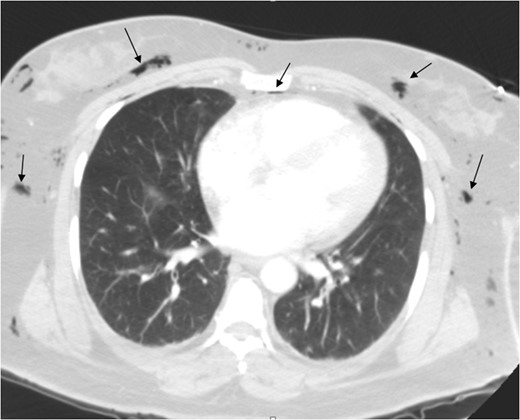

A 46-year-old female, Gravida 3 para 3, all alive, with past medical history of depression, acid reflux and uterine fibroids presented to our emergency unit with acute exacerbation of lower abdominal pain, vaginal bleeding and dizziness, which she had for a month. On examination, her abdomen was soft, with tenderness to right and left lower quadrants. Pelvic examination showed a 14-week uterus, per vaginal bleed and closed cervical os. A repeat sonogram showed the uterus to be 13.9 × 4.8 × 7.1 cm3 with three dominant intramural fibroids. Fundal fibroid measured 3.3 cm, mid posterior uterine fibroid measured 2.2 cm and mid/lower uterine fibroid, 3.8 cm. The central endometrial echo was normal. The right ovary measured ~2.5 × 1.7 × 3.0 cm3 while the left ovary, was 2.5 × 1.9 × 1.7 cm3. Her hematocrit and hemoglobin on presentation were 32% and 11 g/dl, respectively, down from 42% and 14 g/dl a week earlier. She was scheduled for laparoscopic-assisted vaginal supra-cevical hysterectomy with bilateral salpingo-oophorectomy. The operative technique required placing the patient in steep Trendelenburg position and use of a Veress needle through an umbilical incision for insufflation of 3 l of carbon dioxide at a pressure of 15–20 mmHg. All trocal placements were done without complications. Estimated blood loss was 700 ml. The operative time was 7 h (420 min). Surgery was complicated with carbon dioxide overload and retention, with partial pressure of carbon dioxide (PCO2) of 67 mm of mercury (mmHg) immediately post operatively. Patient developed extensive subcutaneous emphysema, and pneumomediastinum (Figs 1–3) on first post-operative Day 1, requiring intubation and mechanical ventilation. Her minute ventilation was increased to wash off the excess CO2. She was sedated and managed expectantly with observation and watchful waiting in the intensive unit. Both subcutaneous emphysema and pneumomediastinum resolved spontaneously by post-operative Day 3 with non-operative treatment. She was eventually discharged in stable condition on post-operative Day 3 and followed up in clinic with no residual issues.

Pneumomediastinum and subcutaneous emphysema as indicated by the arrows.